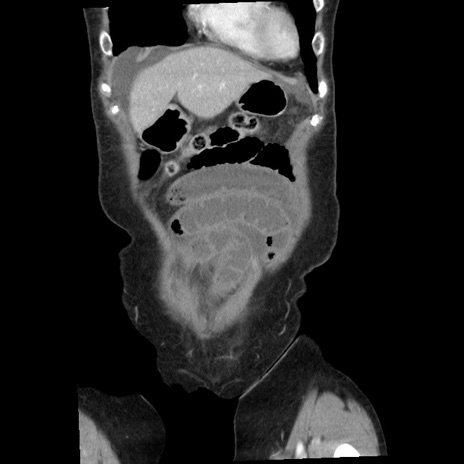

症例1(冠状断像)

【症例】80歳代女性

【主訴】腹痛

【現病歴】8時間前から腹痛あり来院。

【既往歴】糖尿病、脂質異常症、子宮体癌にて子宮全摘術

【身体所見】意識清明・会話良好だが腹痛で苦悶様、全腹部にわたって反跳痛と圧痛あり

【データ】WBC 13600、CRP 0.14、LDH 224、CK 90